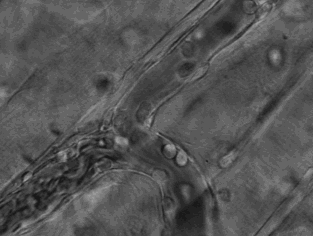

3.這張動(dòng)圖顯示的是嗜酸性粒細(xì)胞在趨化作用的“感知”下逐漸聚集到一只秀麗隱桿線蟲周圍并對(duì)它進(jìn)行攻擊的過程。有“成千上萬”的嗜酸粒細(xì)胞圍聚在線蟲周圍,就像一群螞蟻,善打“包圍戰(zhàn)”。

4.這是中性粒細(xì)胞追擊金黃色葡萄球菌的一個(gè)過程。免疫細(xì)胞捕捉細(xì)菌時(shí)超萌!

5.免疫細(xì)胞也可穿過血管壁奔赴“戰(zhàn)場(chǎng)”,向炎癥和創(chuàng)傷組織處進(jìn)軍、圍剿。